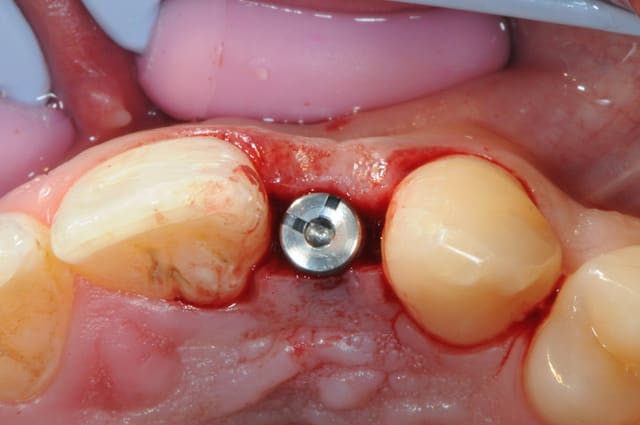

tes implants 12 et 13 n'ont pas le même niveau d'enfouissement, tu n'as pas peur d'une lyse osseuse de 13 pour venir au niveau du col de 12 ?

-cicatrisation de la première vis de cica,

-diamètre plus gros pour la vis de cica

- pilier pour la provisoire

- provisoire moule ION

- ajustage

- polissage soigneux

la suite tout à l'heure, ça sonne à la porte...